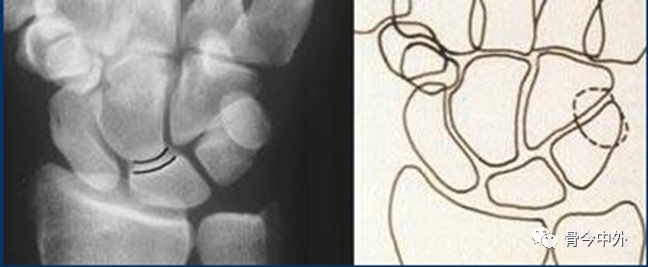

3.腕骨弧线

Gilula 提出三个平滑的弧形勾画出近侧列和远侧列腕骨。弧 I 把舟骨、月骨和三角骨近端关节面连在一起;弧 Ⅱ 勾画出上述骨远端凹面;弧 Ⅲ 由头状骨和钩骨远端凸面所形成。

图16腕骨弧。在正常腕关节背掌位X线片上3个平滑的弧线勾画出近侧列和远侧列腕骨。

图17

腕骨弧线中断;弧线中断提示骨折或韧带断裂导致的半脱位或脱位。上图显示弧线Ⅰ在月骨-三角骨关节处的中断。